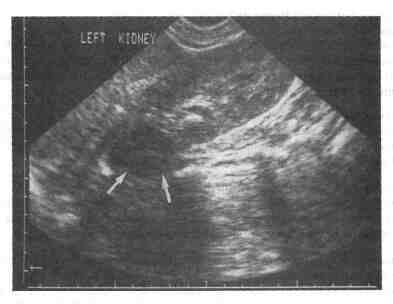

1. С какой частотой работают диагностические ультразвуковые аппараты? 3-15 МГц. 2. Каким образом частота связана с глубиной проникновения излучения в ткани и разрешающей способностью исследования? Чем выше частота ультразвуковой волны, тем меньше глубина проникновения в ткань и лучше разрешение близко расположенных объектов. Аналогично, низкие частоты позволяют повысить глубину проникновения, однако при этом снижается разрешающая способность. Обычно трансабдоминальное ультразвуковое сканирование почек проводят при частоте 3,5 МГц, тогда как для трансректальных методик при исследовании предстательной железы применяют частоту 7,5 МГц. 3. Каким образом границы тканей влияют на прохождение ультразвуковых волн? Ультразвуковые волны проходят сквозь ткани, на границе между ними они отражаются или рассеиваются. Именно это отражение и позволяет определить очертания различных структур. Объекты, не имеющие границ между тканями, ультразвуковые волны проходят беспрепятственно; обычно это заполненные жидкостью образования (например, простая киста почки). 4. Каким образом генерируются ультразвуковые волны? Электрический ток подводится к пьезоэлектрическому кристаллу, что приводит к его колебаниям с развитием ультразвуковых волн. Отраженные ультразвуковые волны ударяются о кристалл, что является причиной возникновения электрического потенциала, который можно преобразовать и представить на экране. 5. Что такое А-режим и В-режим? В А-режиме (амплитудном режиме) интенсивность сигнала представлена в виде пиков различной высоты, расположенных по оси времени или расстояния. В клинической практике прибор, обеспечивающий изображение в одной плоскости, используется редко. В В-режиме (режиме яркости) эхо-сигнал представлен в виде светящейся точки, а его интенсивность определяется яркостью точки. 6. Что такое серая шкала? Используемые в настоящее время ультразвуковые приборы обычно изображают эхо-сигналы на экране в соответствии со шкалой из 64 или 128 единиц яркости. Они обеспечивают двухмерное клинически значимое изображение. 7. Что такое изображение в режиме реального времени? В режиме реального времени датчик постоянно меняет направление, это позволяет быстро получить изображение в В-режиме, что вызывает у исследователя ощущение "живого" изображения, аналогичного таковому при рентгеноскопии. 8. Объясните цель допплеровского исследования. Что представляет из себя цветной потоковый допплер? Допплеровское изображение позволяет одновременно осуществлять наблюдение в режиме реального времени и измерять уровень кровотока. Эффект Допплера, или допплеровский сдвиг, описывает изменение частоты звуковой волны после отражения от движущегося объекта. Эритроцит — одиночный движущийся объект, который рассеивает одиночную звуковую волну. Сочетанный эффект множества отраженных волн воспринимается датчиком и передается на экране в виде цветного изображения (обычно синего и красного) поверх серой шкалы в зависимости от повышения или понижения частоты отраженных волн, т. е. в зависимости от направления движения эритроцитов — от датчика или к датчику. 9. Дайте ультразвуковые характеристики кисты почки. Обычная киста почки — это объемное образование, связанное с почкой. Внутри кисты нет отражения эхосигналов, стенки кисты тонкие и окружают ее со всех сторон, в области стенки кисты определяется дорсальное усиление ультразвуковых волн. 10. Дайте ультразвуковые характеристики опухолей почек. Опухоли почек — это объемные образования, связанные с почками, часто изменяющие строение их полостных систем. Обычно их внутренняя структура неоднородна, контуры нечеткие, в некоторых случаях эти образования сложно отличить от почечной паренхимы. 11. Помогает ли ультразвуковое исследование в диагностике гидронефроза? Обычно центральный эхокомплекс, соответствующий срединной части почки и воротам почки, является гиперэхогенным за счет жира и сосудистых образований. В гидронефротически трансформированной почке полостная система расширена за счет мочи (жидкости), которая может быть легко выявлена с помощью ультразвука. Ультразвуковое изображение является ценным методом диагностики, позволяющим определить расширение полостной системы почки и диагностировать гидронефроз. 12. Дайте ультразвуковые характеристики камня. Обычно конкременты мочевых путей определяются